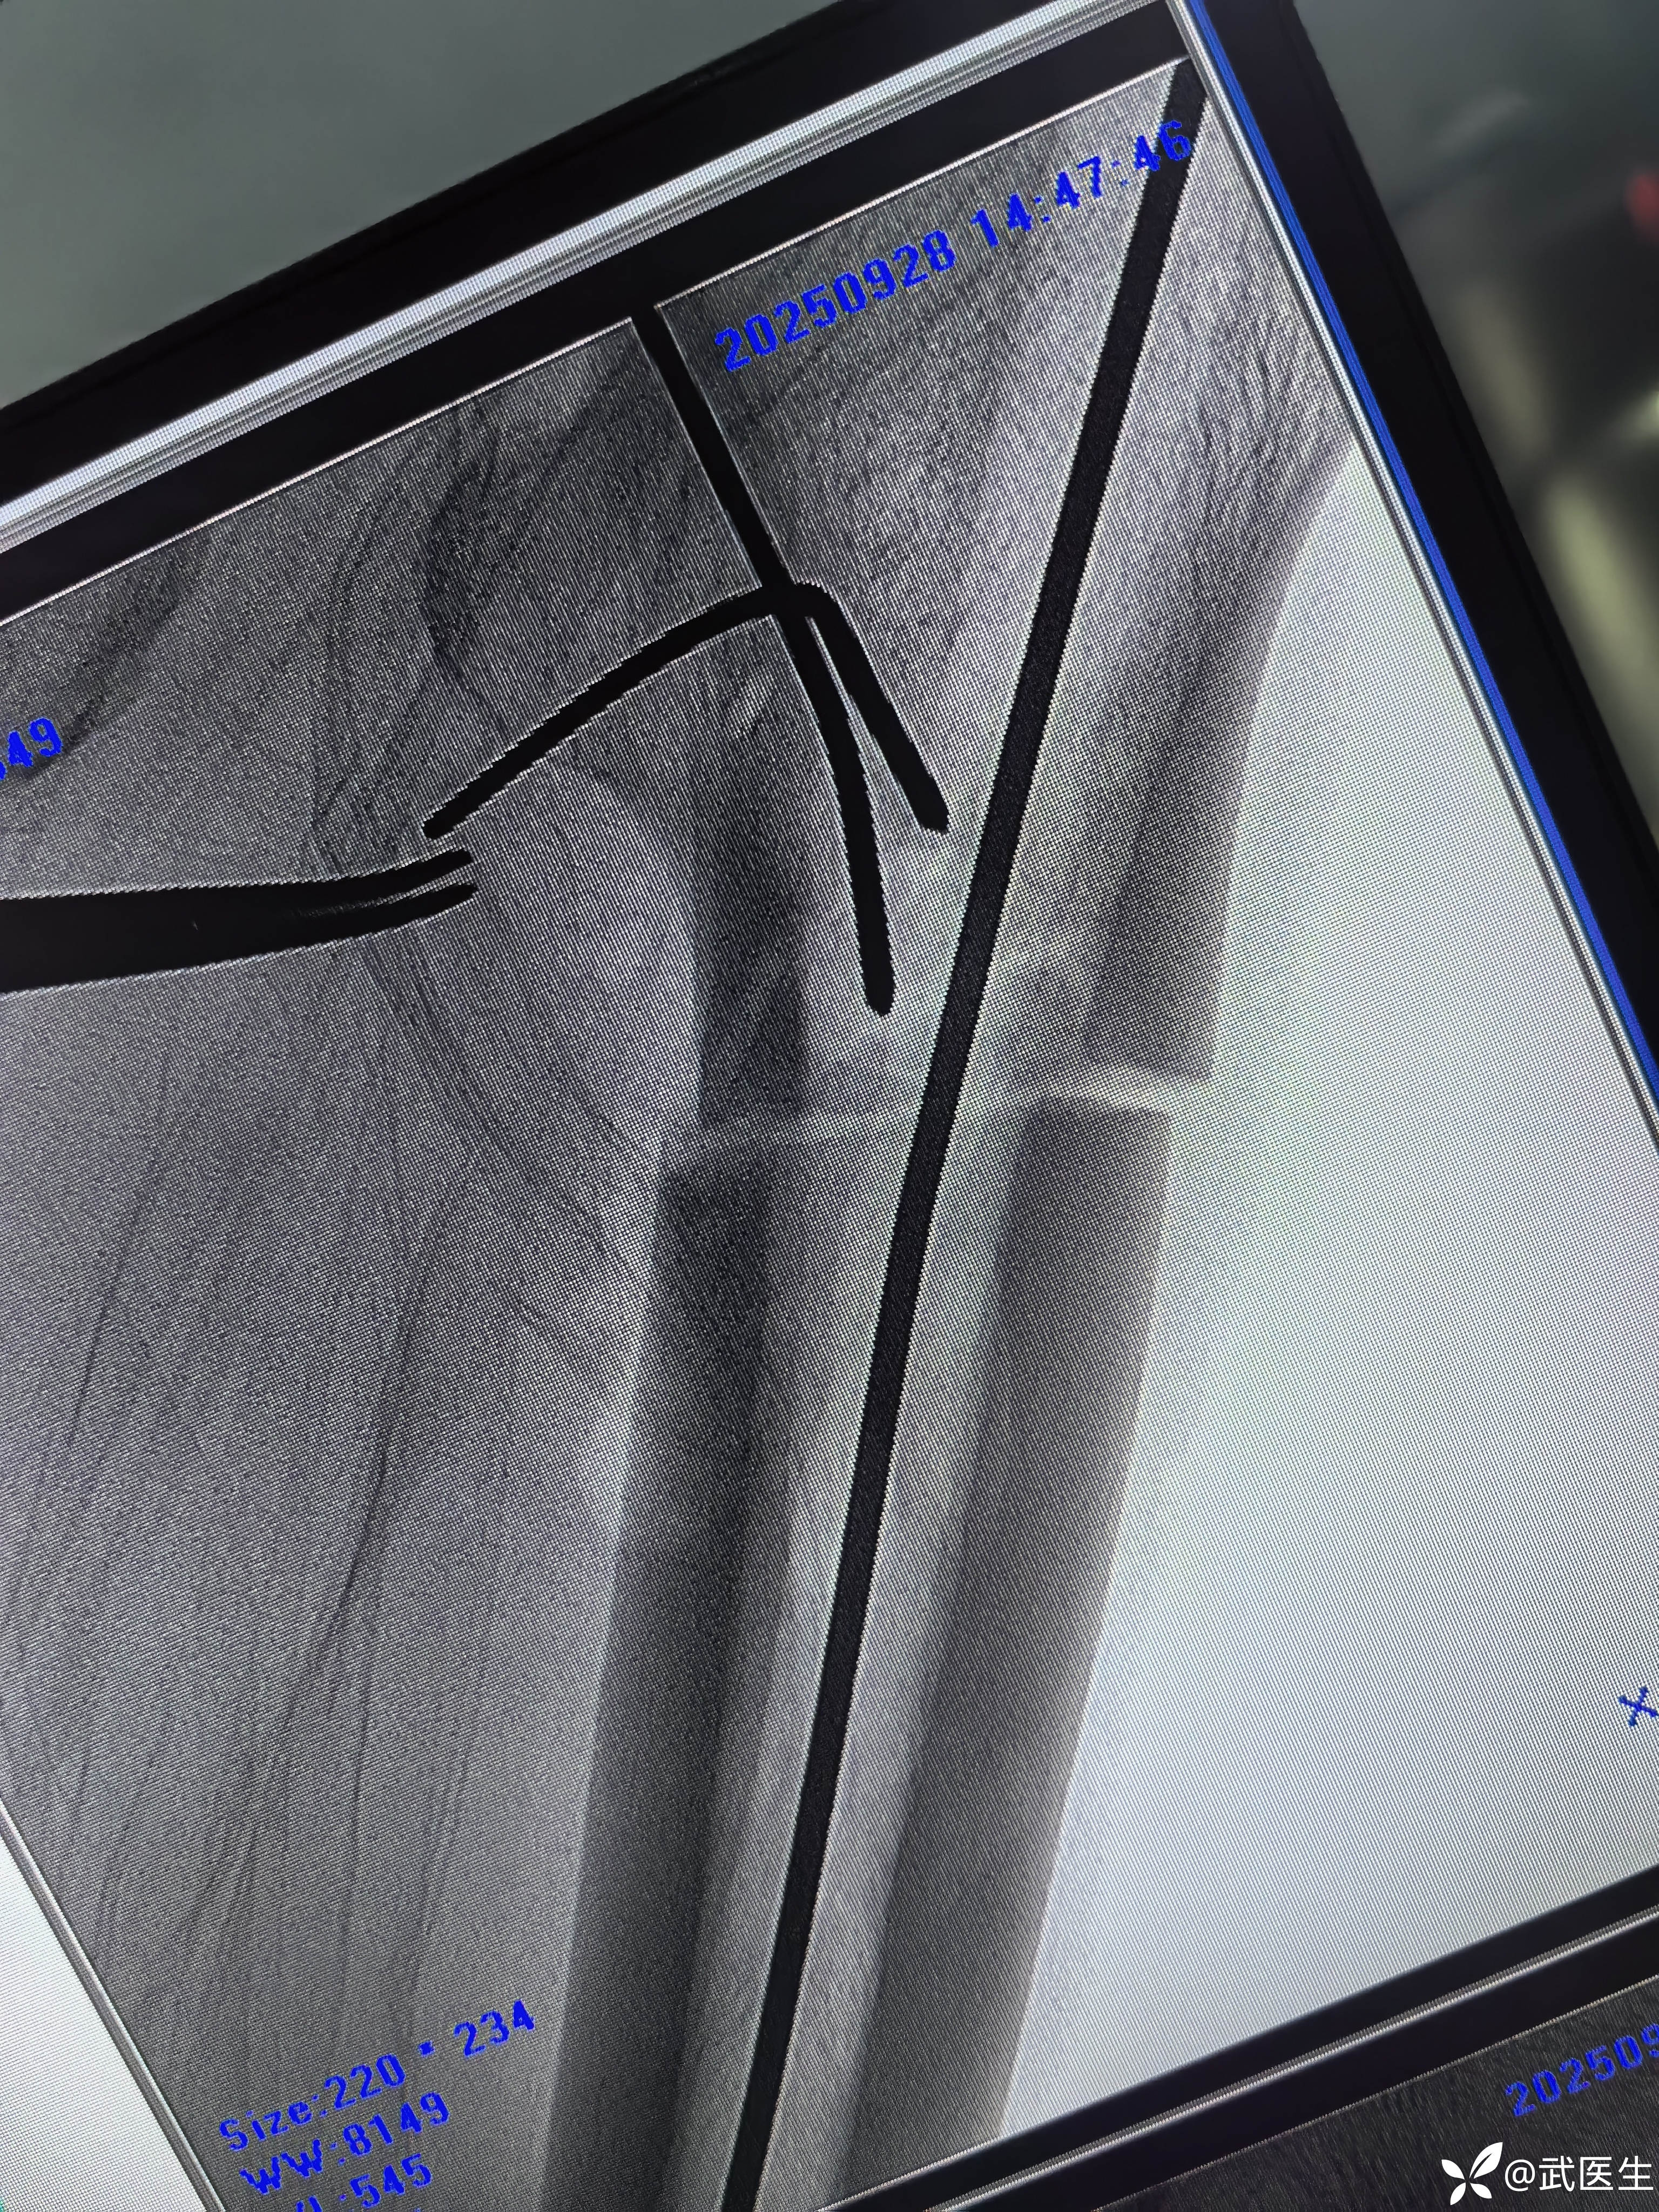

髓内钉已经很深了,头钉有点偏上,不再更换短钉了

阻挡克氏针更换为阻挡钉

最终

头钉有点偏上,髓内钉也算顶天立地。

股骨近端骨折髓内钉经常遇到向外侧成角,不好纠正,即便复位良好情况下扩髓后,置钉位置能不满意,此时阻挡克氏针是一个不错的办法。